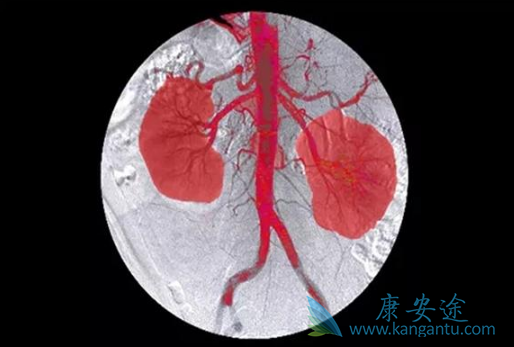

由于卡博替尼(Cabozantinib)作用的分子靶点很多,部分靶点参与了骨转移的形成,因此卡博替尼具有不错的控制实体瘤骨转移的能力。这个结论,近期已经得到了有力的支持。(1)肾癌骨转移:多国际多中心III期METEOR研究中,一组接受卡博替尼治疗,一组接受依维莫司治疗。两组无疾病进展生存时间7.4个月 vs 2.7个月,中位总生存时间,也是卡博替尼组更高。

在同时合并骨转移和内脏转移的患者中,卡博替尼组和依维莫司组的中位生存时间,差异更大。此外,针对骨转移的疗效,卡博替尼20%的患者骨转移明显好转,而依维莫司组这个比例只有10%,又是翻倍的优势!副作用方面,两组3-4级不良反应发生率,卡博替尼略高:73% vs 51%。但是卡博替尼组,发生骨折、截瘫、骨痛等骨转移相关的不良事件的概率更低,从29%降低到了23%。

(2)前列腺癌骨转移:1028名晚期前列腺癌患者,2:1分组,一组接受卡博替尼(Cabozantinib)治疗,一组接受传统标准方案患者。结果显示:虽然卡博替尼相比于标准治疗,未能大幅度延长患者的总生存期。但是,对于控制骨转移而言,卡博替尼的疗效非常棒。用药3个月后评估骨转移明显缓解的概率,传统治疗只有3%,而卡博替尼有42%,提高了14倍!